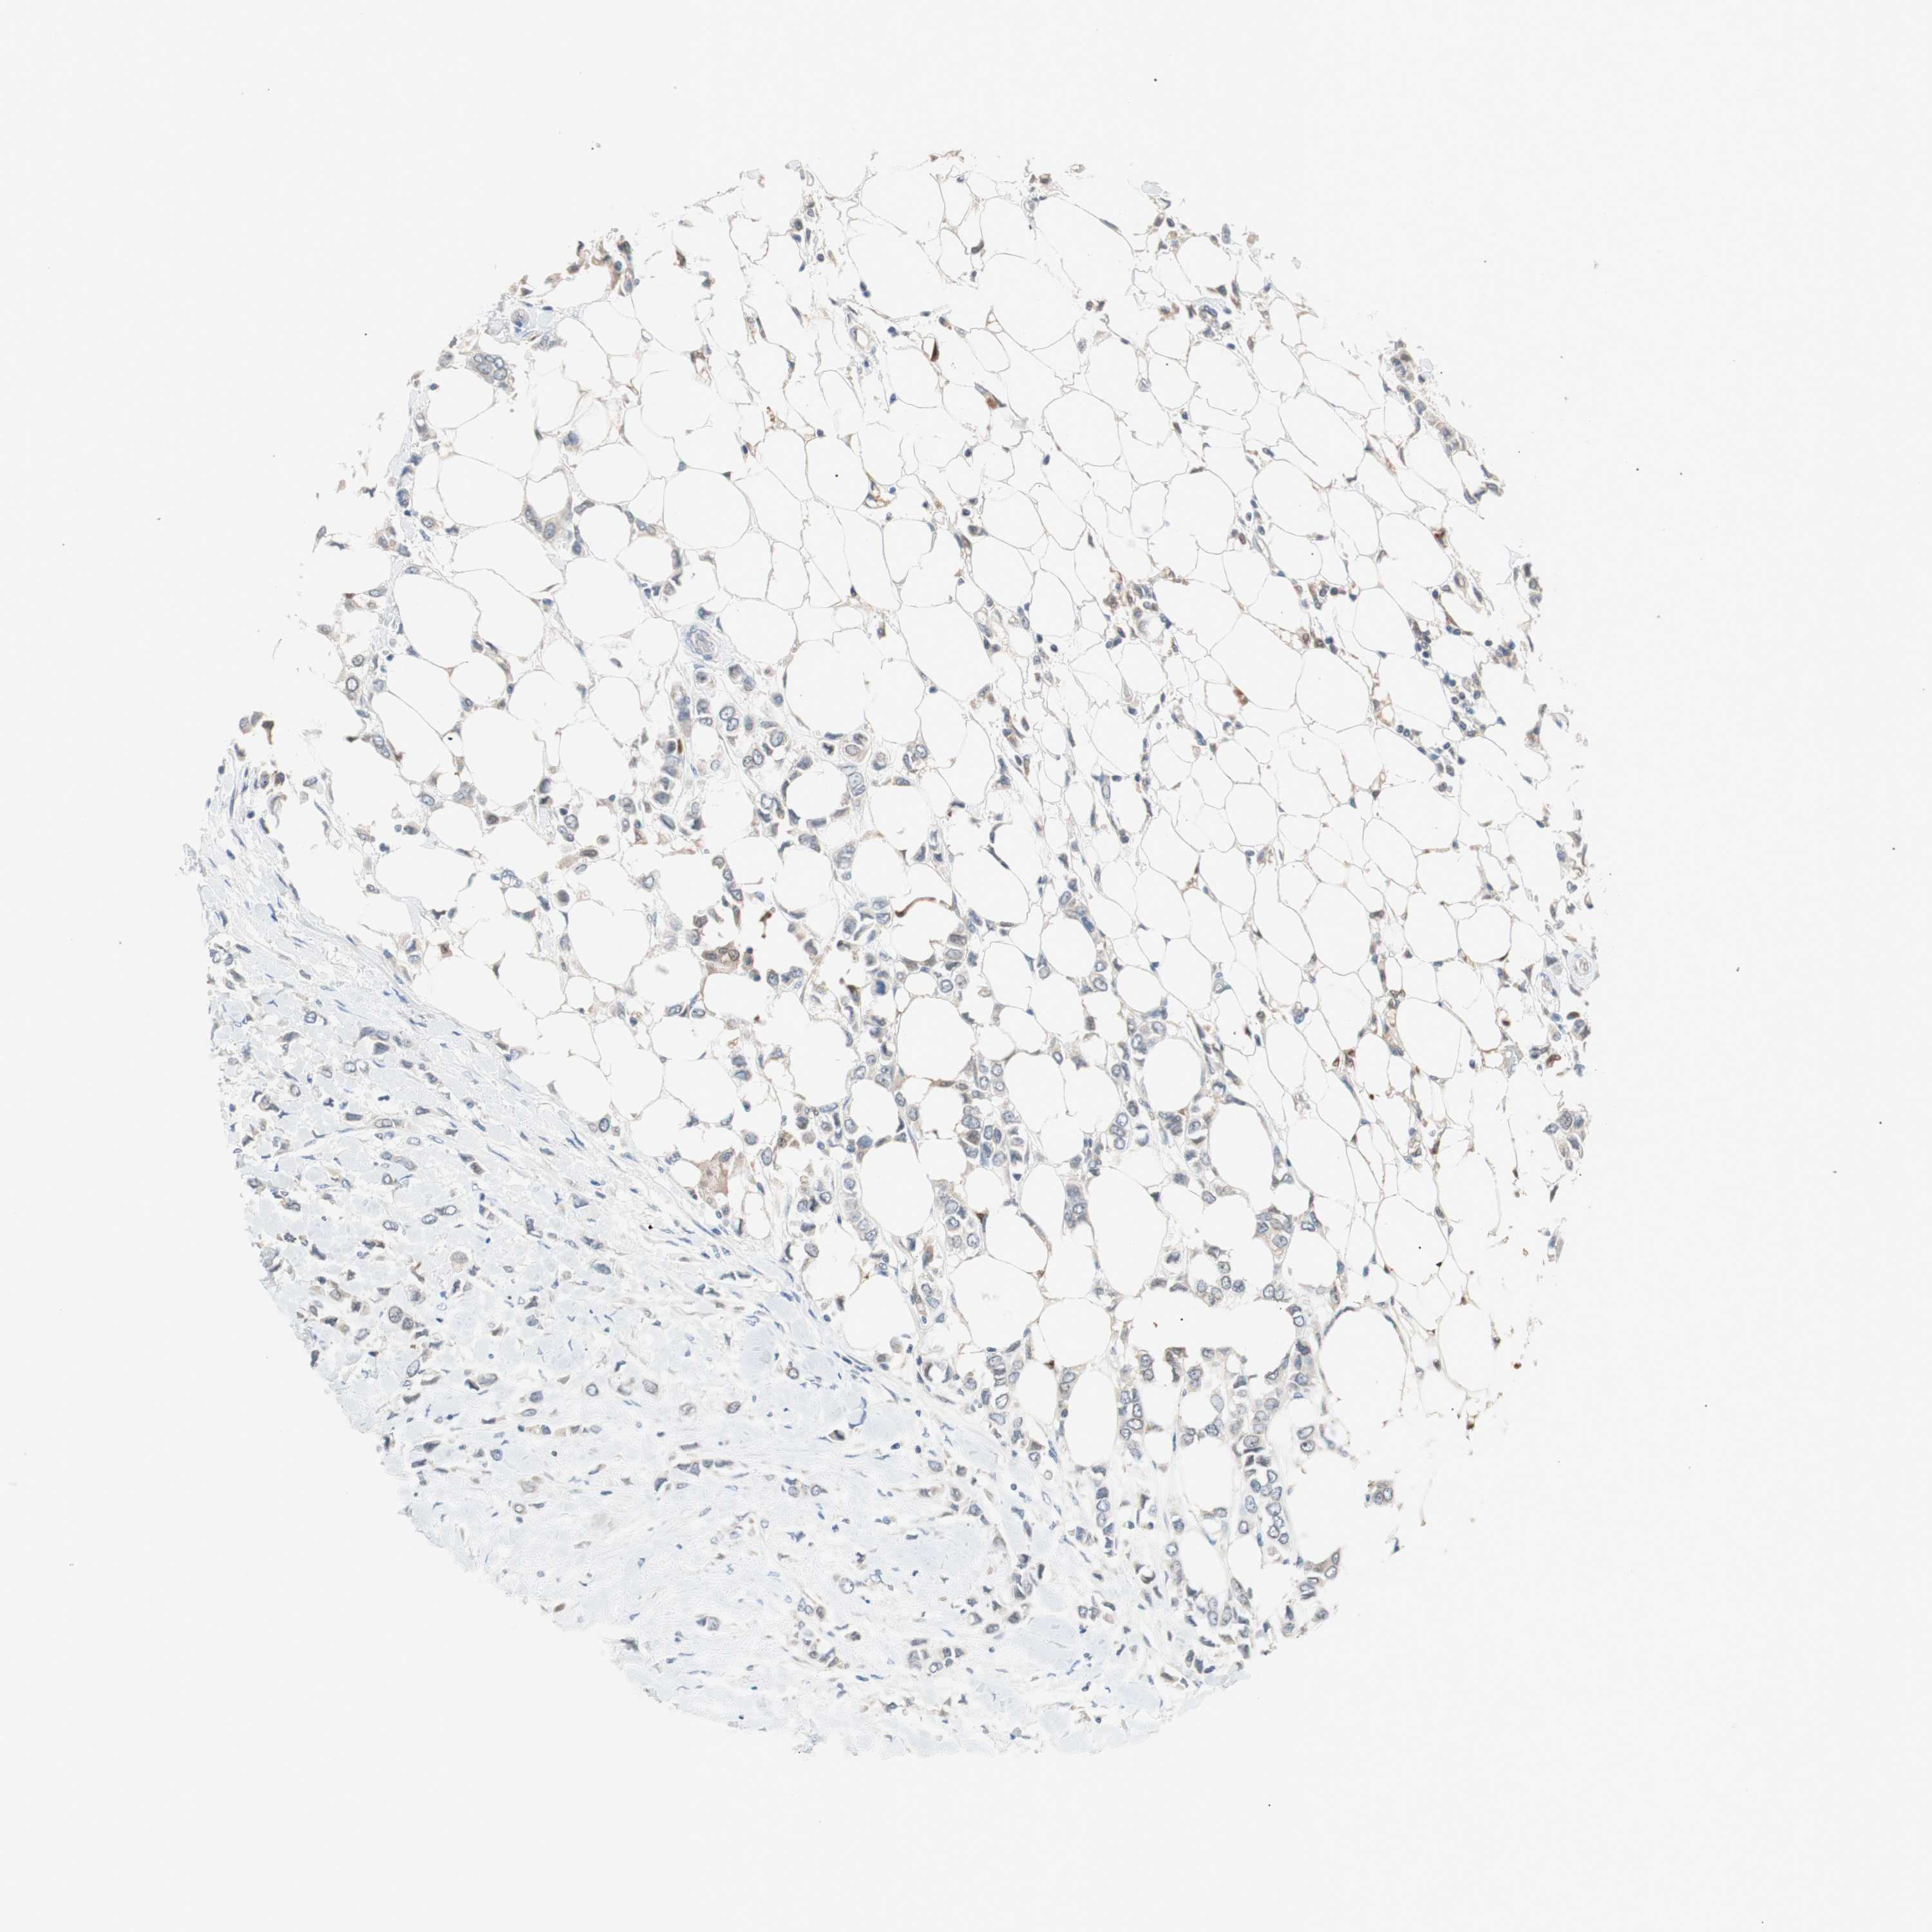

CANCER BREAST CANCER Show tissue menu

BRCA TCGA BRCA VALIDATION PROTEIN EXPRESSION